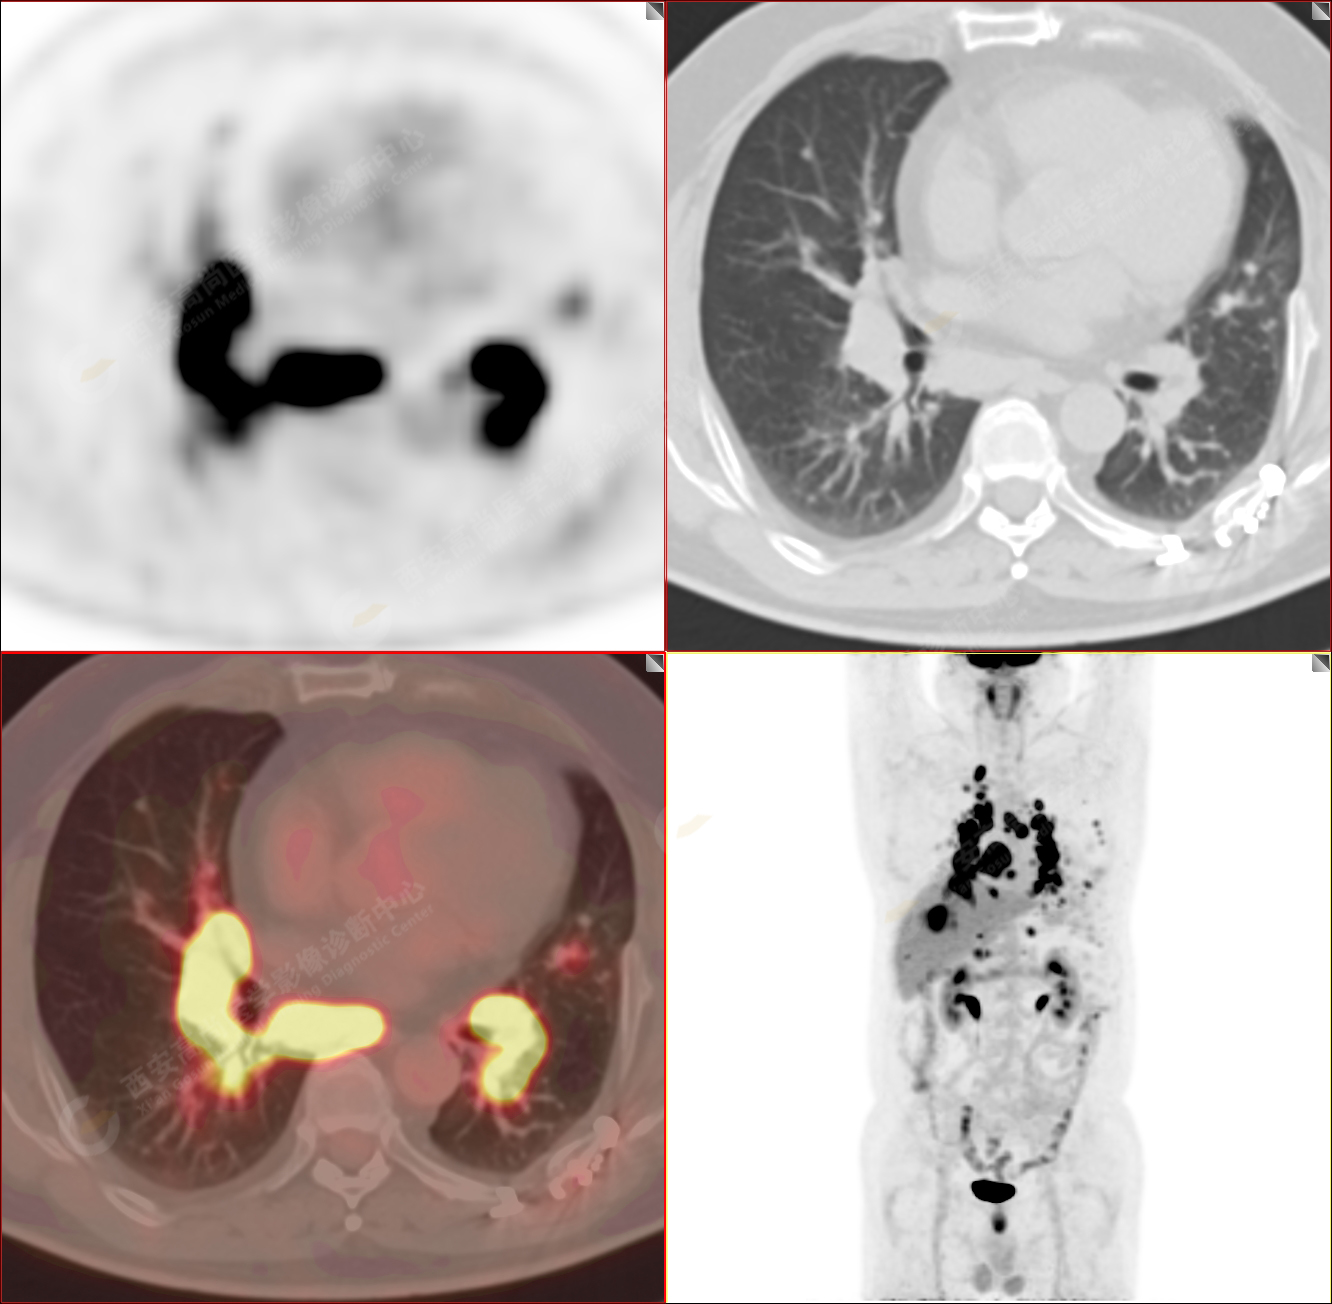

男性,53歲,頭暈半月入院,CT發(fā)現(xiàn)肺內(nèi)腫塊,雙肺多發(fā)大小不等實(shí)性及粟粒樣結(jié)節(jié),雙肺門(mén)及縱隔多發(fā)腫大淋巴結(jié)。病程中無(wú)發(fā)熱、胸悶氣及胸部不適。既往:左側(cè)肋骨外傷史。

PET-MR圖像